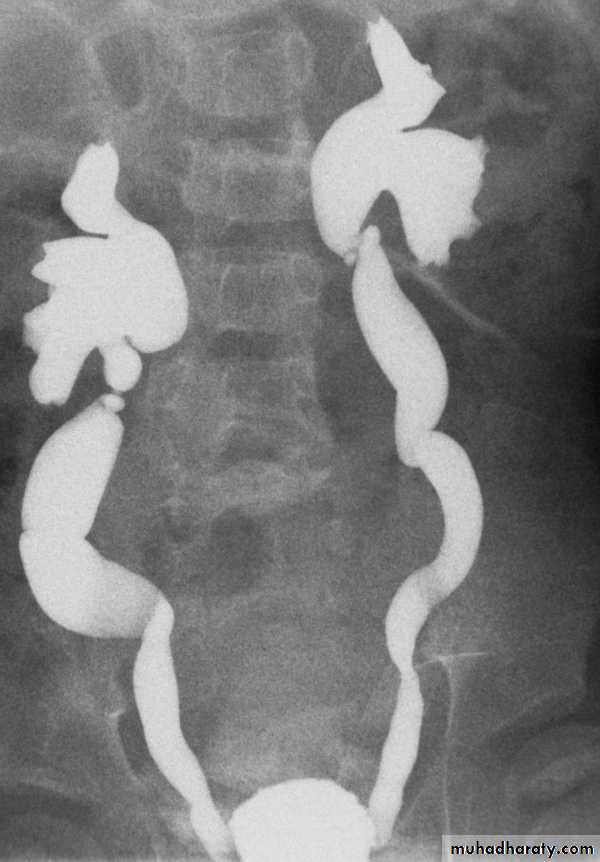

Bifid collecting system :- Most frequent.

- Unilateral or bilateral.

- Incomplete; sometimes only pelvis is bifid , 10 %of population, (not significant)

- Complete; (1-2 % of population), two ureters may be separate down to their insertion into the bladder.

Upper moiety ureter inserts inferior and medial to its normal site, or ectopically to vagina or urethra leading to urine incontinence if beyond urethral sphincter, may associate with obstruction or uretrocele.

- Lower moiety ureter inserts into normal anatomical position, usually associated with reflux.